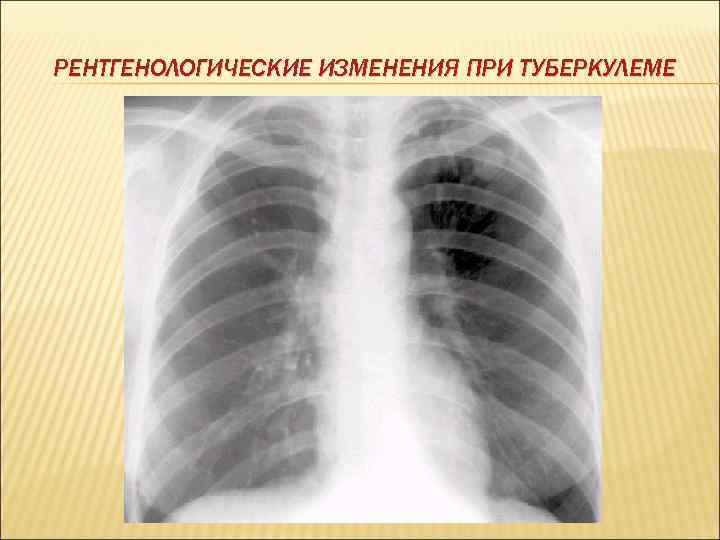

ТУБЕРКУЛЕМА Различного генеза инкапсулированное, с преобладанием казеоза образование, более 10 мм в диаметре, с малосимптомным течением. Туберкулема чаще всего локализуется в легких, но может также возникать в лимфатических узлах, почках, мозге, половых органах встречается у лиц молодого и зрелого возраста. Различают туберкулемы: по строению: гомогенные, конгломератные, слоистые; по количеству: единичные, множественные. По течению: туберкулемы со стабильным течением – длительное время остаются у больных без динамики туберкулемы с регрессирующим течением – медленно уменьшаются и постепенно на их месте образуются очаги, фиброзные изменения; туберкулемы с прогрессирующим течением – это туберкулемы, у которых со временем появляется распад.

РЕНТГЕНОЛОГИЧЕСКИЕ ИЗМЕНЕНИЯ ПРИ ТУБЕРКУЛЕМЕ